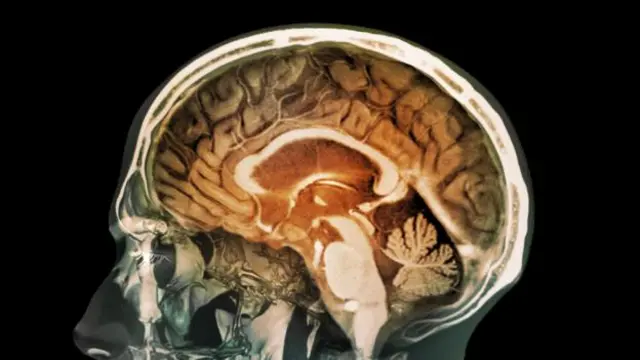

1970’lerde Beatles grubunun plak şirketi olarak bilinen EMI’de mühendis olarak çalışan Godfrey Hounsfield röntgen yoluyla beynin içini görmeyi başardı. Yani bugünkü tomografinin temeli atılmış oldu.

Bugün beyni taramada kullanılan teknolojiye fonksiyonel manyetik rezonans görüntüleme ya da kısaca ‘emar’ (fMRI) deniyor. Daha sonra UCL Üniversitesi’nden nörolog Joe Devlin beyin taramasını benim üzerimde uyguladı.

Bu taramada beyindeki oksijen değişimi hareket halinde görebiliyor. Beynin bir kısmı belli bir iş üzerinde yoğunlaşmışsa, örneğin kelime ya da dille ilgili bir çalışma yapılıyorsa o bölgede enerji kullanıldığı için kan akışı artmaktadır. İşte fMRI tarayıcısı bu kan akışını gözler.

Yapılan işe göre beynin aktif olan kısımlarındaki renk değişimini tarama sırasında ekranda görmek mümkün oluyor.

Örneğin ne söyleyeceğinizi düşünürken beynin farklı bir bölgesi, sayı sayma gibi düşünme gerektirmeyen monoton bir işlemde farklı bir bölge aktif hale gelir.

Daha önceleri doktorların tek bilgisi beyninde hasar olan bir hastanın sorununun nerede olduğu ve bunun ne tür bir arızaya yol açtığından ibaretti. Fakat beyin taraması sayesinde nörologların sağlıklı bir beyni görüp farklı kısımlarının nasıl kullanıldığını ve aralarındaki ilişkiyi anlaması mümkün oluyor.